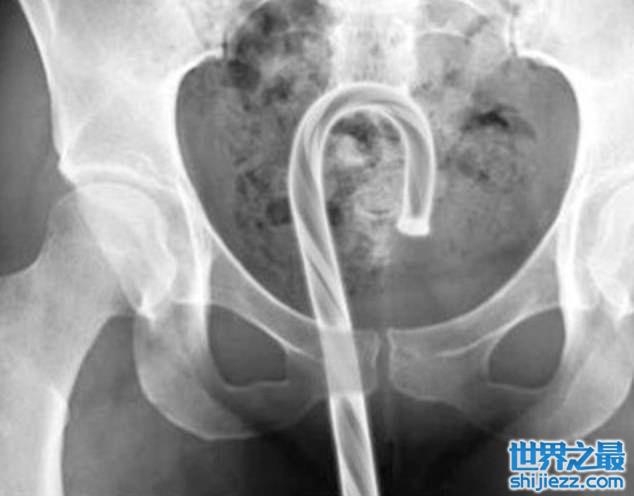

在印度曾经有一位男子因为腹部痛送到急诊室,没想到X光一照竟然发现里面有一团电线。在医生的逼问下,他才坦诚是之前为了助兴才塞进去的,没想到却卡在里面只好摆着,没想到却让自己变成排尿有困难。